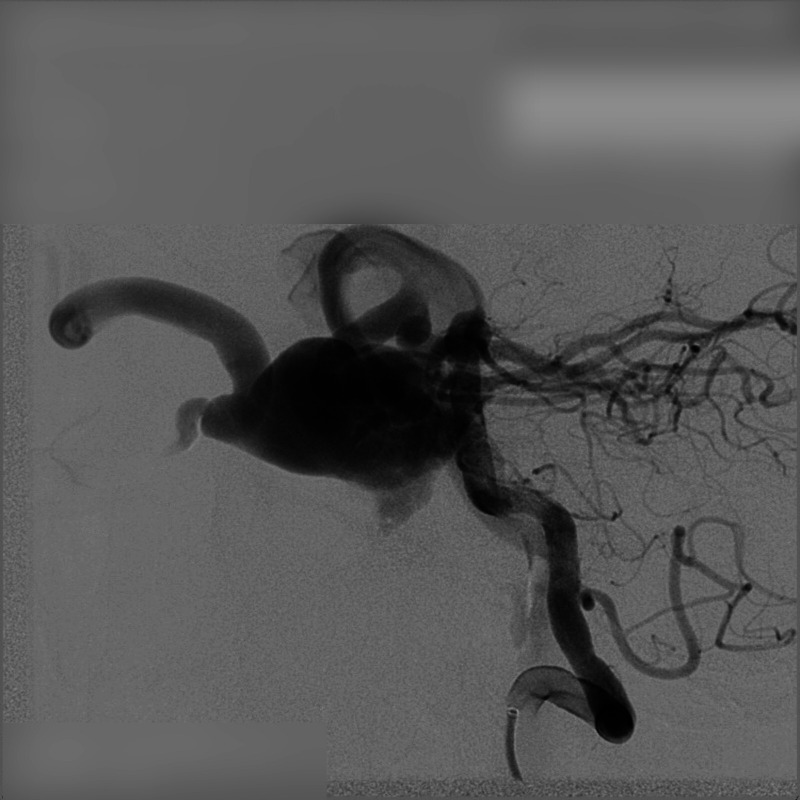

颈海绵状瘘(CCFs)是颈动脉和海绵窦之间异常的动静脉连接,由外伤引起。本病例报告提出一位47岁男性,在道路交通事故后发展为CCF。患者表现出搏动性眼球突出和眼球杂色等症状,这是CCFs的特征。通过数字减影血管造影(DSA)确认诊断,显示瘘的来源。患者采用显微手术和血管内介入治疗的新方法,包括内颈动脉结扎和经动脉线圈栓塞。治疗后症状迅速缓解,包括搏动性眼球突出和眼压。本病例强调了多学科方法的重要性,结合显微外科和先进的血管内技术,有效地治疗创伤性CCFs。该研究强调了早期诊断的价值和微创手术在改善患者预后方面的作用。

Carotid-Cavernous Fistulas (CCFs) are abnormal arteriovenous connections between the carotid artery and the cavernous sinus, resulting from trauma. This case report presents a 47-year-old male who developed a CCF following a road traffic accident. The patient exhibited symptoms such as pulsatile exophthalmos and an ocular bruit, characteristic of CCFs. Diagnosis was confirmed through Digital Subtraction Angiography (DSA), revealed the origin of the fistula. The patient was treated using a novel combined approach of microsurgery and endovascular intervention, involving ligation of the internal carotid artery and transarterial coil embolization. The treatment resulted in rapid resolution of symptoms, including the pulsatile exophthalmos and ocular bruit. This case highlights the importance of a multidisciplinary approach, blending microsurgical and advanced endovascular techniques, in effectively managing traumatic CCFs. The study underscores the value of early diagnosis and the evolving role of minimally invasive procedures in improving patient outcomes.